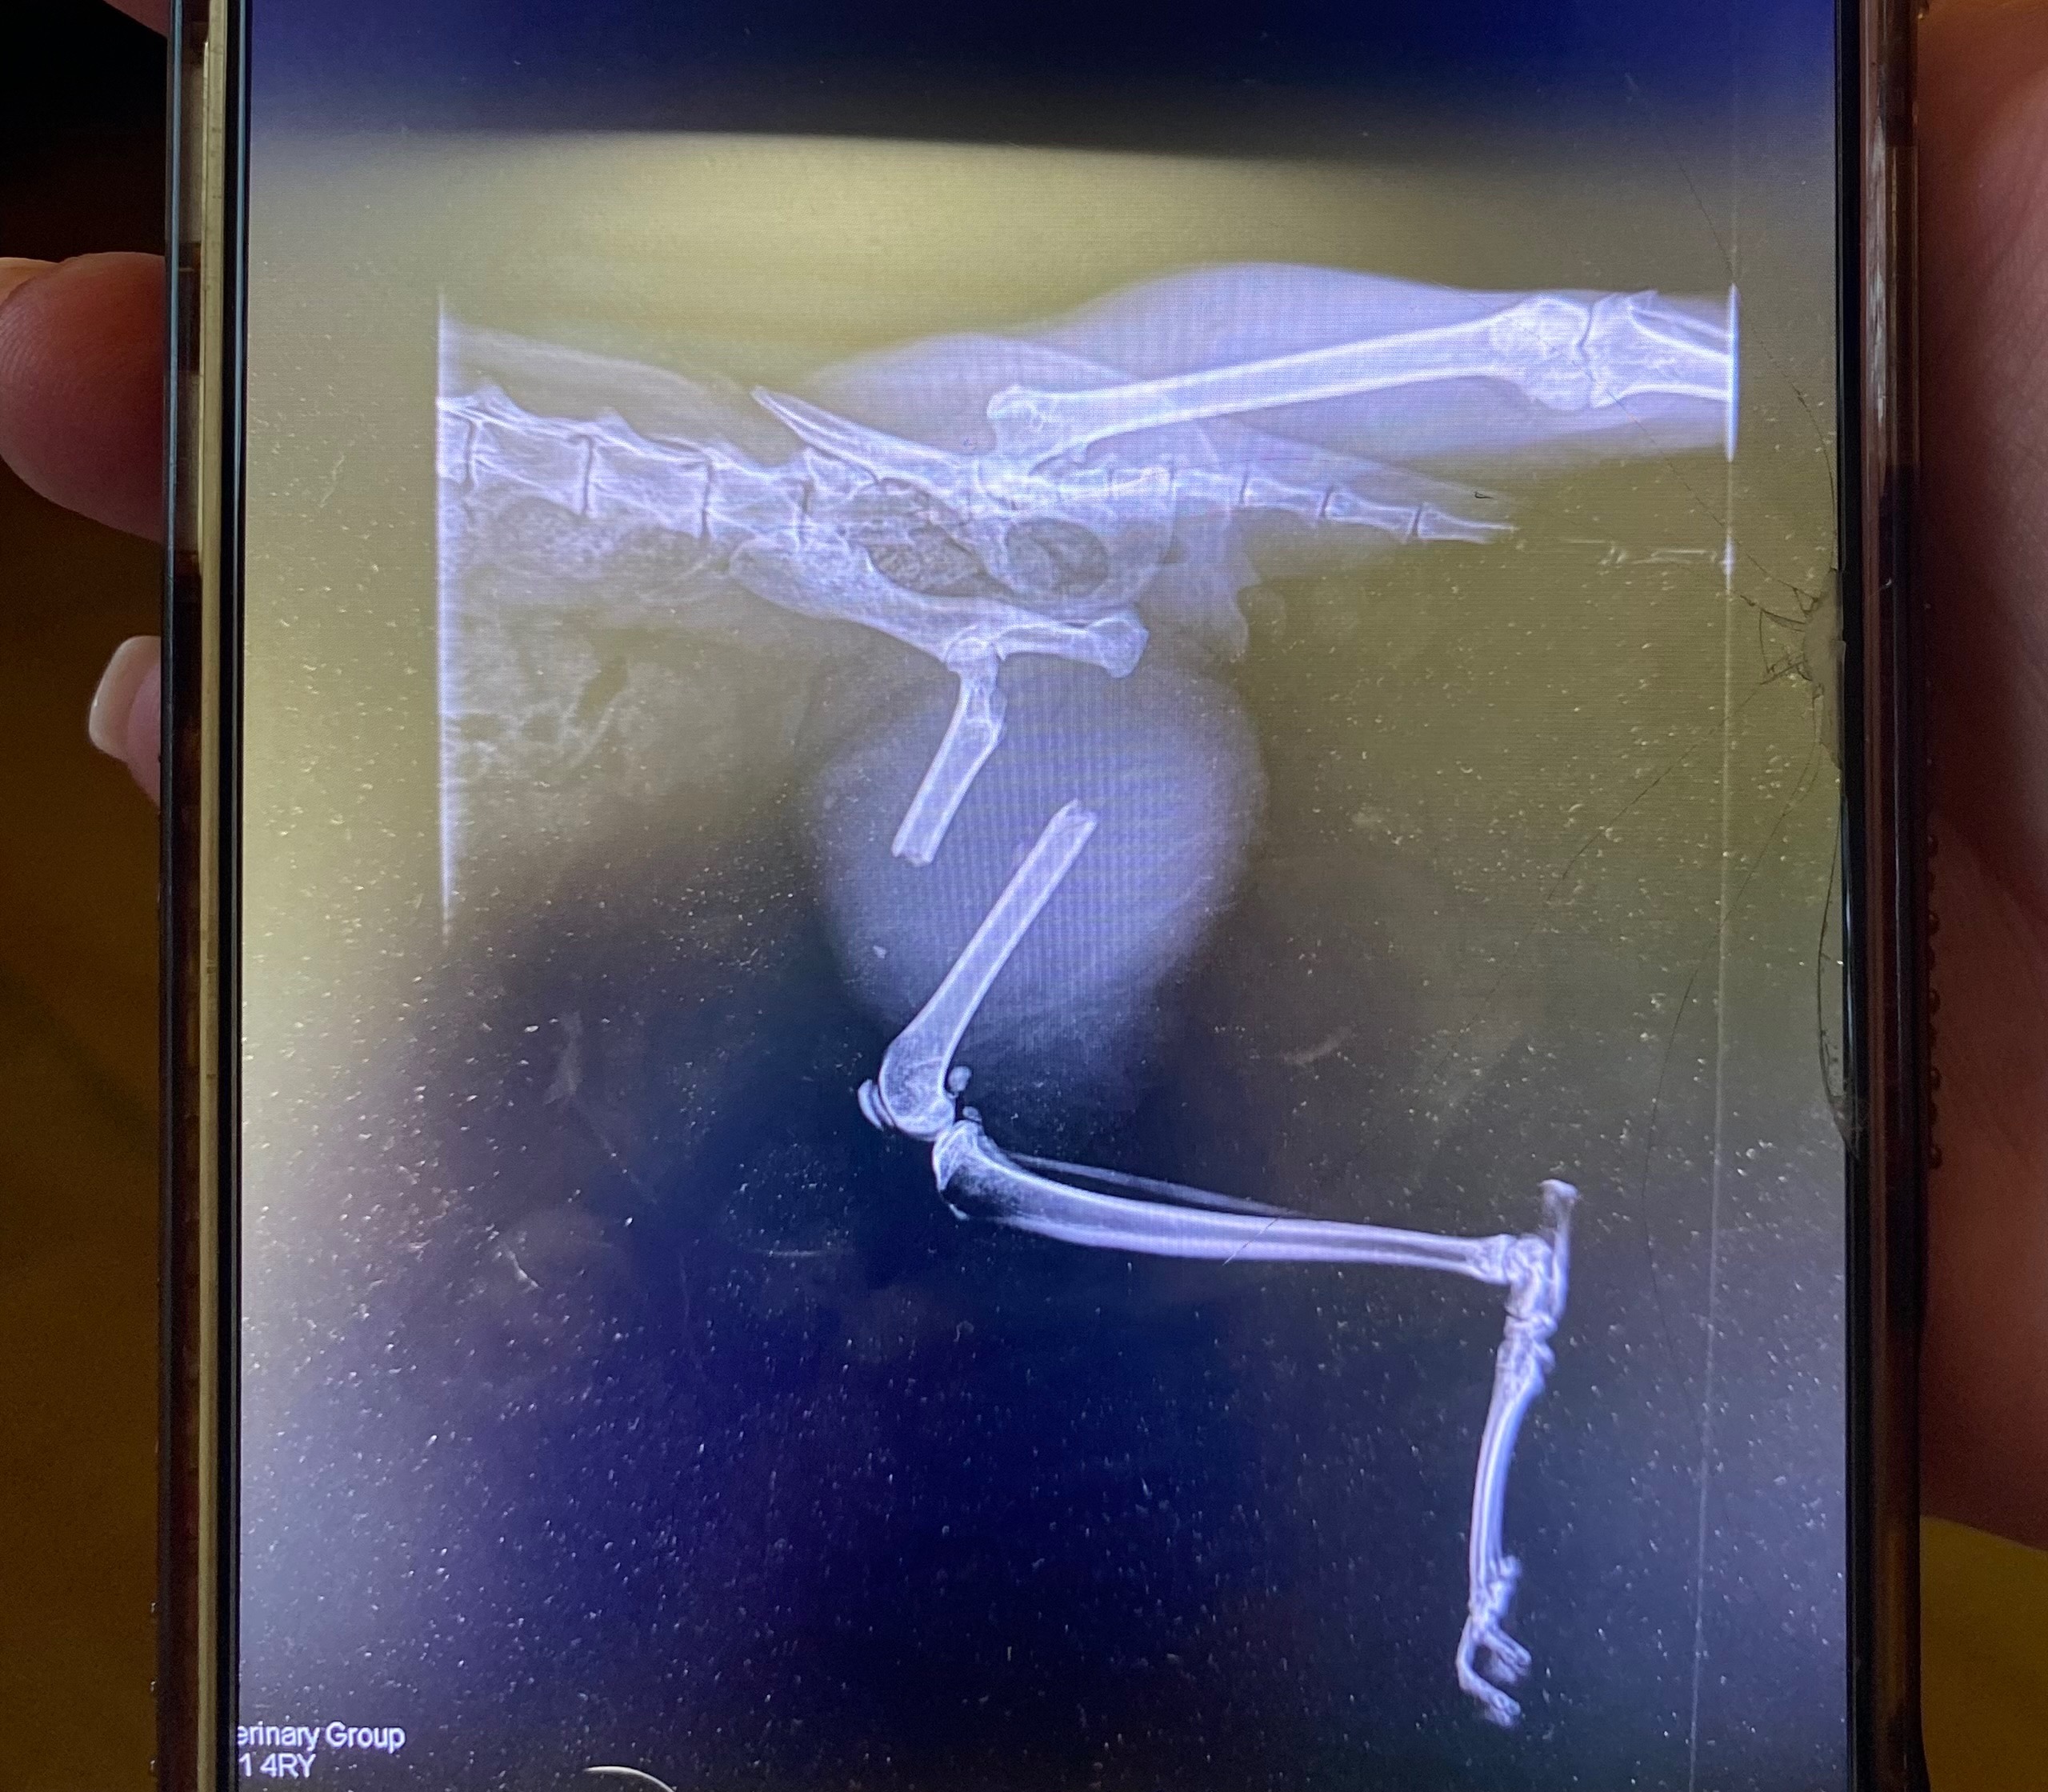

Hi, my name is Wendy and we are fundraising to help save our beautiful boy, Simba. He’s broken his leg clean in half and needs surgery to survive. We cannot afford to fix the leg and we can’t afford to amputate, our options are to put him down or raise money to amputate. We’ve been through the mill this year (builder stole £60k of our savings and we plunged all our life savings into fixing the renovation from hell, all whilst I was on maternity leave with our 10 month old, Willow), so our savings are too low to be able to save him.

If we fund raise £1000 we can’t save his leg, but we can save him. He is so calm, and sweet natured. He’s wonderful with our two babies. He grew up with dogs and somehow adopted their obedience. He comes when called, he is not a fussy eater, he comes / follows us on walks through the village, he thinks he is a dog! We have to do everything we can to save him, which includes spending what we have left and asking for help from everyone we know.